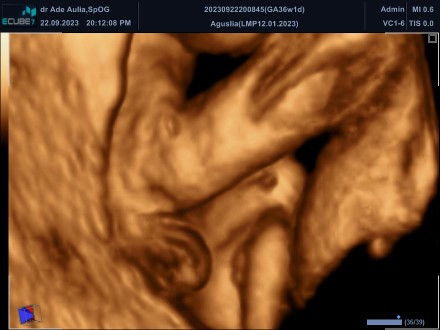

Itu beneran JK Perempuan apa gimana ya Bun? UK 8 bulan, USG 4D, takut nanti salah ngarep bun